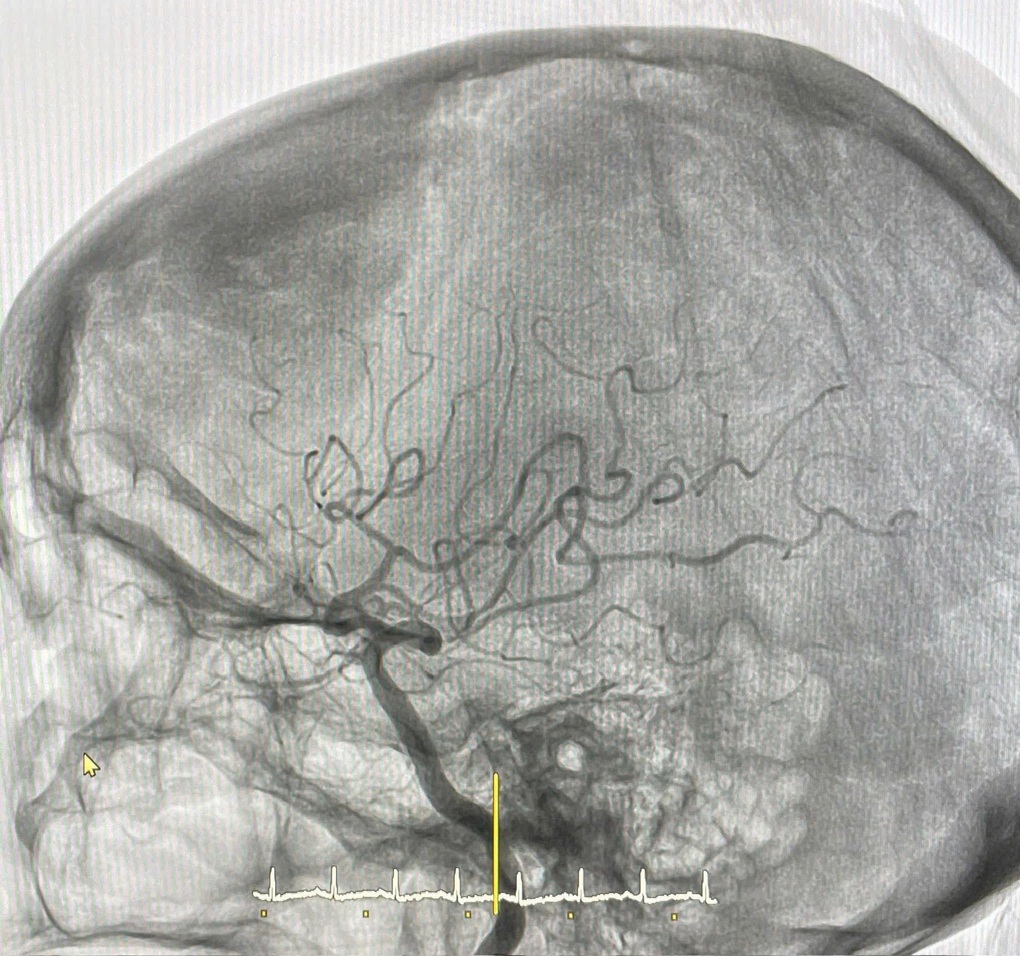

نتایج نشان داد که ترومبوز، قطعه M1 شریان مغزی میانی راست را به طور کامل مسدود کرده است.

تیم تصمیم گرفت عمل ترومبکتومی مکانیکی انجام دهد. کل فرآیند به خوبی پیش رفت، رگ کاملاً بازگشایی شد و جریان خون پس از انسداد دوباره برقرار شد و شرایط بهینه برای بهبودی بافت مغز باقی مانده ایجاد شد.

اسکن مغز بیمار (عکس: ارائه شده توسط بیمارستان).